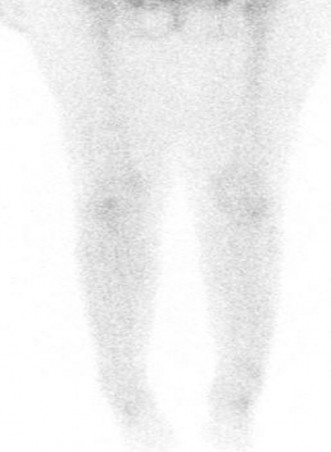

A typical MRI image showing bone marrow edema consistent with a sacral insufficiency fracture. The high signal on STIR sequences highlights the fracture line, often elusive on plain radiographs.